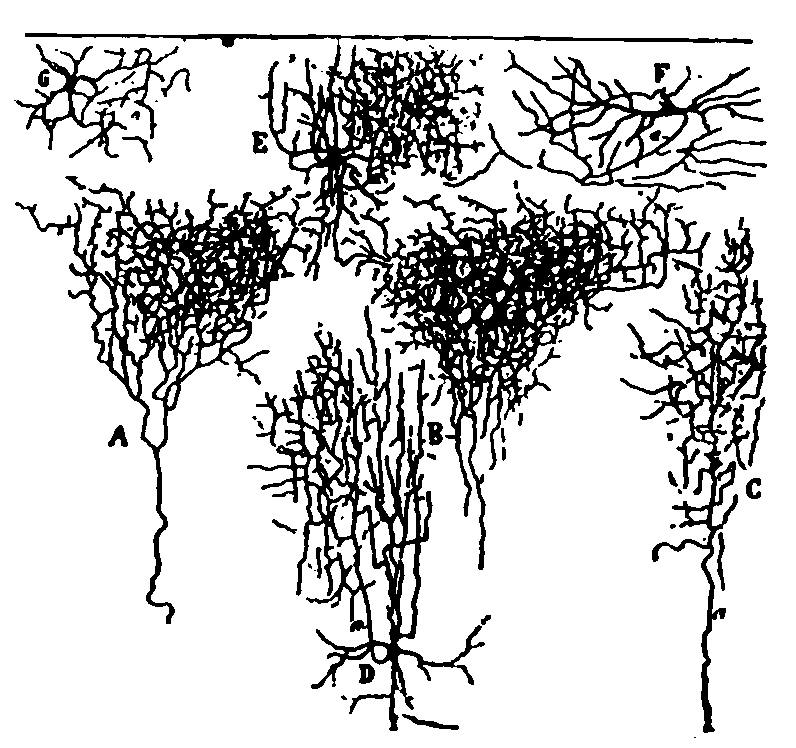

| 3. | Small and medium-sized pyramidal cells of the visual cortex of a child twenty days old | 110 |

| 4. | Series of sections showing the fine nerve endings and branchings of the first and second layer of the visual cortex of a child fifteen days old. | 111 |

| 5. | First, second and third layer of the anterior central convolution of the brain of a child one month old | 112 |

| 6. | Layers of the posterior central or ascending parietal convolution of a new-born child | 112 |

| 7. | Diagram of cells of cerebral cortex | 113 |